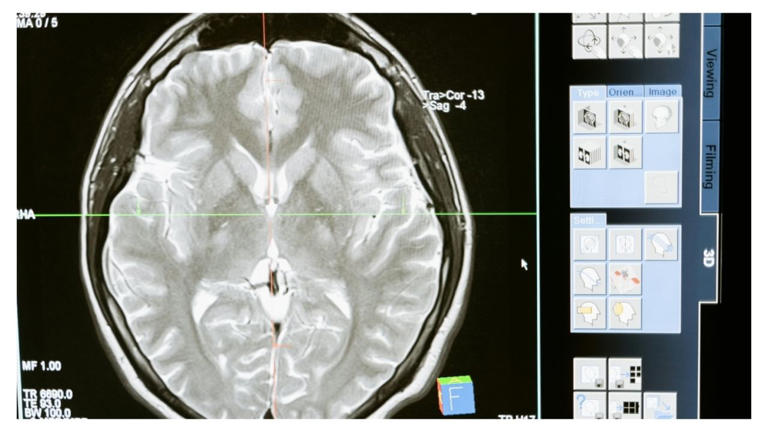

Highresolution image of brain scans showing differences in mental ...